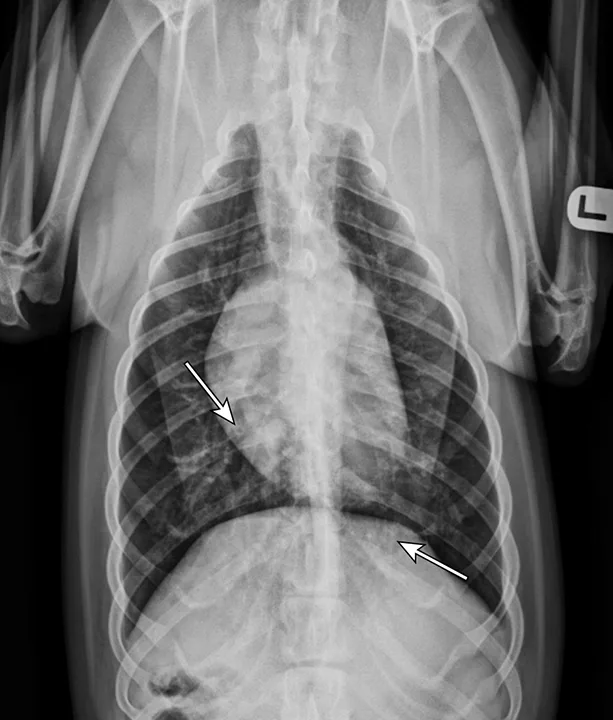

Thoracic radiographs showing a characteristic diffuse, patchy bronchointerstitial pattern (arrows)

Thoracic radiographs revealed a moderate, diffuse, bronchointerstitial pattern (Figure 1). The cardiac silhouette, pulmonary vasculature, and extrathoracic structures were normal. Airway sampling via bronchoscopy was recommended based on radiographic findings. CBC and serum chemistry profile were performed prior to sedation. Serum chemistry results were within normal limits. CBC revealed leukocytosis (24.3 x 103/µL; normal range, 4.9-17.6 x 103/µL) characterized by marked eosinophilia (10.4 x 103/µL; normal range, 0.07-1.49 x 103/µL), monocytosis (1.4 x 103/µL; normal range, 0.13-1.15 x 103/µL), and band neutrophilia (729/µL; normal range, 0-170/µL). Heartworm antigen test was negative.

Thoracic radiographs are generally characterized by a diffuse bronchointerstitial pattern with peribronchial cuffing and thickening of the bronchial walls. In some cases, bronchiectasis or alveolar infiltration may be observed.2,6-8 Occasionally, patchy pulmonary opacities create a nodular appearance.4 Radiography is critical for ruling out other common causes of cough and/or acute respiratory distress. Concurrent disease processes (eg, cardiomegaly, tracheal collapse) can complicate diagnosis.